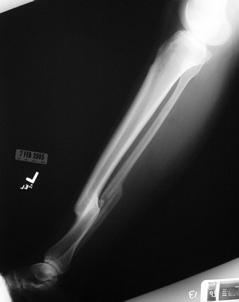

She complains of vague knee and back pain, which worsen with activity or prolonged standing. She is now 55, recently retired, but otherwise healthy and desires to hike, ski and exercise. She was injured 20 years earlier after being struck by a car. Other injuries included a ruptured spleen, and an early post-injury pulmonary embolism. Her tib-fib fx was treated in a cast. Her tibial shortening measures 2.5 cm on scanogram. Attached are today's films.